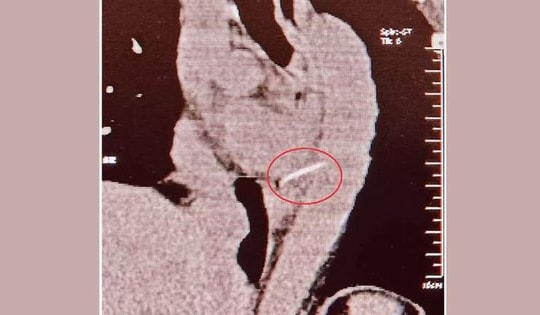

Người phụ nữ 54 tuổi đau ngực dữ dội, bác sĩ sốc nặng khi gắp ra thứ "đáng sợ" bên trong

30/09/2025 04:00

Người phụ nữ 54 tuổi đã vô tình nuốt phải một chiếc xương cá dài 4cm. Sau đó, bà bị đau ngực dữ dội và được đưa đến bệnh viện.